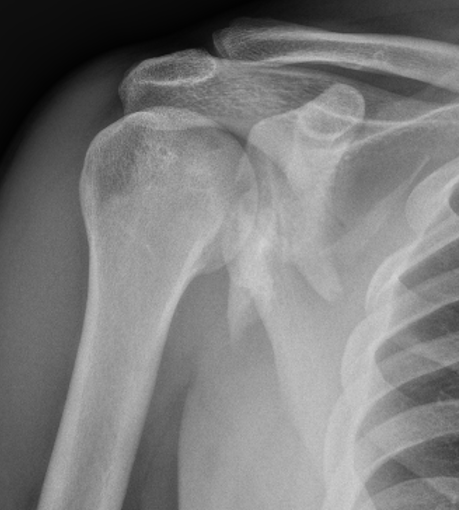

Scapula blade fractures

Indications for surgery

| Glenoid neck displacement | Glenoid neck angulation | Glenopolar angle |

|---|---|---|

| > 2cm medial displacement | > 45° angular deformity | < 22° glenopolar angle |

Medial displacement

Angulation

Glenopolar angle

Definition

- line connecting the superior and inferior glenoid fossa

- line connecting the superior pole of glenoid and inferior angle scapula

- normal 30 - 40 degrees